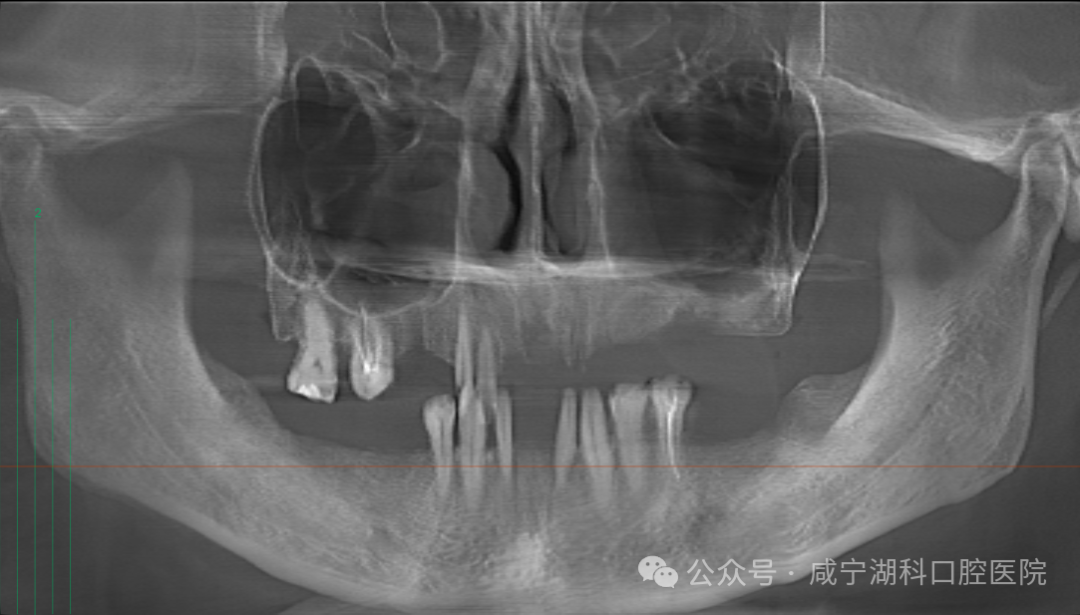

家住崇阳的胡阿姨,因牙齿缺失多颗,说话漏风,常年只能吃一些软烂食物,去过多家医疗机构治疗修复都没有达到效果,还因骨头条件太差被告知无法种植,于是胡阿姨抱着试一试的心态来到湖科口腔医院寻求解决办法。

“想做种植牙,但是他们说我牙槽骨太薄,已经没办法再种了。”胡阿姨回忆道,此刻,她的口腔内,上颌仅剩4颗牙,下颌磨牙全部缺失,严重影响了进食和社交,生活品质一落千丈。

刘伟院长根据胡阿姨的牙齿情况,分析到上颌窦剩余骨量非常少,做种植有两种方式,一种是采用上颌窦外提升,需要大量植骨,要忍受大半年至一年的无牙期,而且要进行两次手术才能完成修复。第二种是穿翼种植,是一种新技术,目前咸宁掌握这项种植技术的医生很少,这项技术是拔完牙后即刻就进行穿翼种植,只用一次手术就能完成种植,当天就能戴牙,大大缩短修复时间,减少无牙痛苦。

拍摄口腔CT,进行专业分析